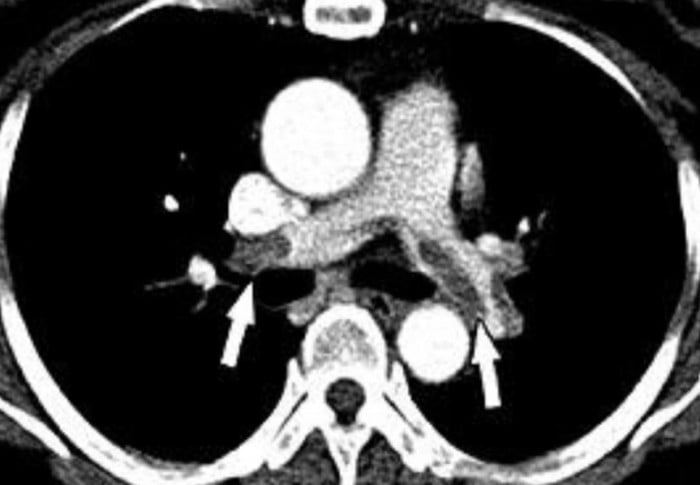

Theo báo cáo, bệnh nhân ban đầu hồi phục bình thường nhưng chỉ sau khoảng 48 giờ xuất hiện khó thở, tụt huyết áp, giảm oxy máu. Ban đầu, ê-kíp nghi ngờ phản vệ độ 3, tuy nhiên kết quả thăm khám và cận lâm sàng cho thấy người phụ nữ bị thuyên tắc mỡ và thuyên tắc phổi do mỡ - một biến chứng cực kỳ nguy hiểm của hút mỡ.

Các chuyên gia cho biết thuyên tắc mỡ là biến chứng ít gặp nhưng tỷ lệ tử vong cao, thường xuất hiện trong 24 đến 72 giờ sau phẫu thuật hút mỡ. Khi mỡ xâm nhập vào tuần hoàn, chúng có thể di chuyển đến phổi hoặc các cơ quan quan trọng, gây tắc nghẽn, viêm mao mạch và tổn thương nặng nề hệ hô hấp, tuần hoàn.